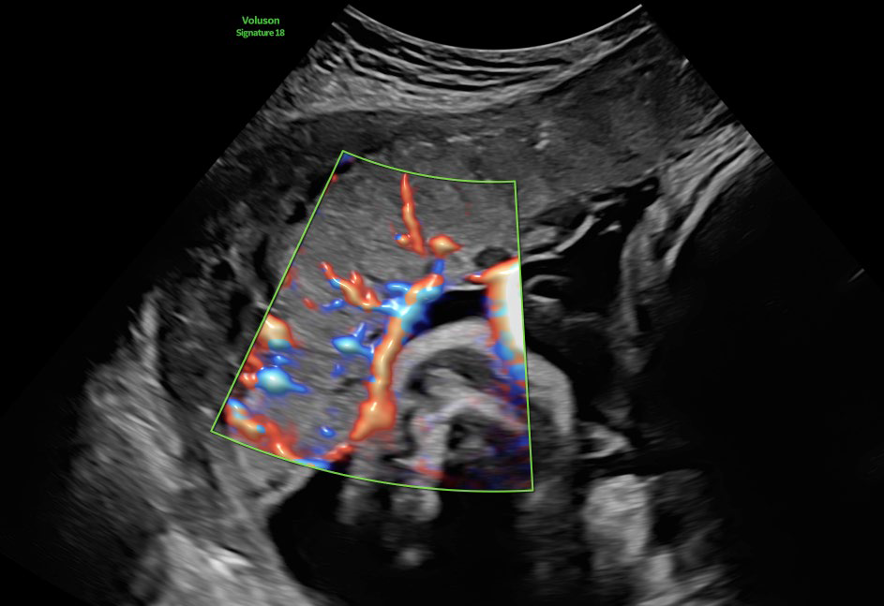

• RadiantflowTM

Separación mejorada entre vasos sanguíneos que proporciona la percepción de un flujo sanguíneo dinámico, añade información de altura y profundidad para una apariencia 3D, Menos destellos, límites vasculares mejorados e Identificación fácil y rápida incluso de los vasos más pequeños.